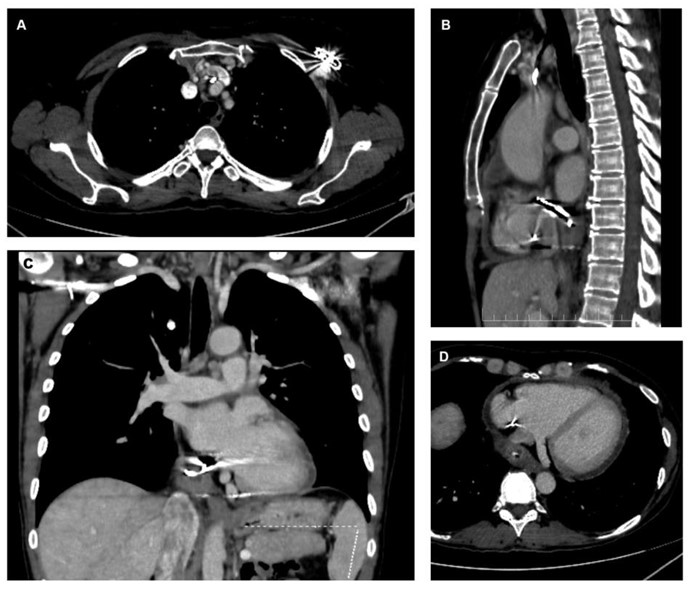

The patient was subsequently admitted to the Internal Medicine Department, and a contrast-enhanced computed tomography (CT) of the body was performed. The scan revealed that the atrial lead of the pacemaker traversed the inferoposterior wall of the RA. The lead tip appeared to be located within the pericardial sac, surrounded by a centimeter-sized fluid collection suggestive of abscess formation (Fig. 2A-D). The vena cavae were dilated, and the pericardium demonstrated mild enhancement and effusion suggestive of probable pericarditis.

Contrast-enhanced CT scan showing (A) axial view of the pacemaker generator area with venous thrombus adjacent to the leads, (B) sagittal view with extravascular lead trajectory, (C) coronal view of the abscessed area in the pericardial sac, and (D) axial view showing the relationship of the abscess to the coronary sinus and inferior vena cava.